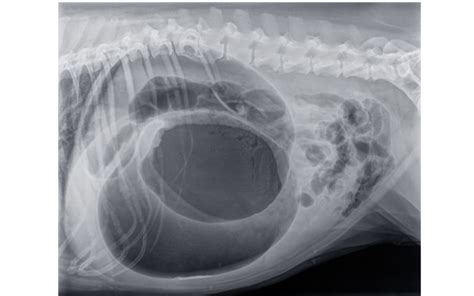

Torzia žalúdka

Nepríjemný jav, počas ktorého dochádza k postupnému pretočeniu žalúdka o 180 až 360 stupňov okolo jeho osi. Hromadí sa v ňom jedlo, tekutiny a plyny, ktoré nemajú ako postupovať ďalej do čriev. Príčiny sú aj genetické, torzia sa vyskytuje skôr u veľkých plemien. Torzia žalúdka sa vyskytuje najmä pri väčších plemenách psov so širokým hrudníkom. Ide o akútny, život ohrozujúci stav, pri ktorom sa psovi pretočí žalúdok. Dochádza k nemu najmä ak pes zožerie naraz väčšie množstvo jedla, vody a následne sa prudko pohybuje. Žalúdok sa nafúkne, pretiahne a pretočí sa okolo svojej osi. Dochádza k priškrteniu pažeráka a okolitých ciev, čo má za následok ešte väčšiu tvorbu plynov a odumieranie vnútorných orgánov v dôsledku nedokrvenia.

Liečba: torziu žalúdka je nutné okamžite riešiť s veterinárom. Je to život ohrozujúci stav. Torzia žalúdka si vyžaduje okamžitý zásah veterinára.

Prevencia: torzii žalúdka u psov, ako sú dogy, retrievery a ďalšie veľké plemená, môžete predísť tak, že tesne po jedle psovi doprajete aspoň polhodinový odpočinok.